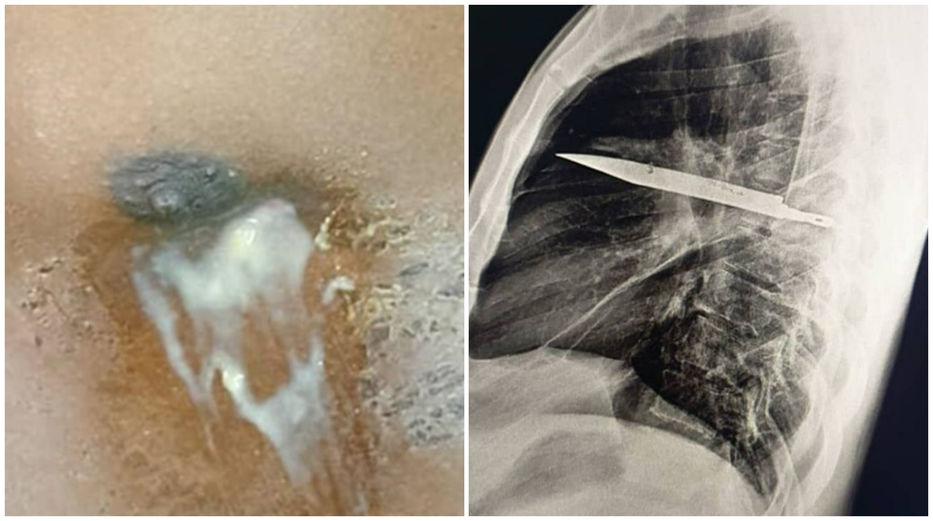

El reporte describe lo sucedido con un hombre de 44 años y “sano en términos generales”, que llegó al hospital con un historial de diez días de secreción de pus blanco desde el pezón derecho.

En aquel momento, los médicos suturaron sus heridas y desde ese momento en adelante vivió una vida sin sobresaltos, hasta que su pezón comenzó a supurar pus. Incapaces de determinar a simple vista la causa de la infección, los médicos ordenaron un examen de rayos X y se sorprendieron al ver una enorme hoja de cuchillo alojada en el pecho del hombre.

Los médicos explicaron que el pus se debía a la acumulación de tejido muerto alrededor del cuerpo extraño, y se maravillaron de que el hombre hubiera vivido ocho años con semejante pieza metálica en el cuerpo sin sentir molestias.